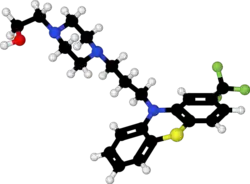

| Formula | C22H26F3N3OS |

| Molar mass | 437.53 g·mol−1 |

| 3D model (JSmol) | |

Fluphenazine is a typical antipsychotic of the phenothiazine class.[2] Its mechanism of action is not entirely clear but believed to be related to its ability to block dopamine receptors.[2] In up to 40% of those on long term phenothiazines, liver function tests become mildly abnormal.[6]